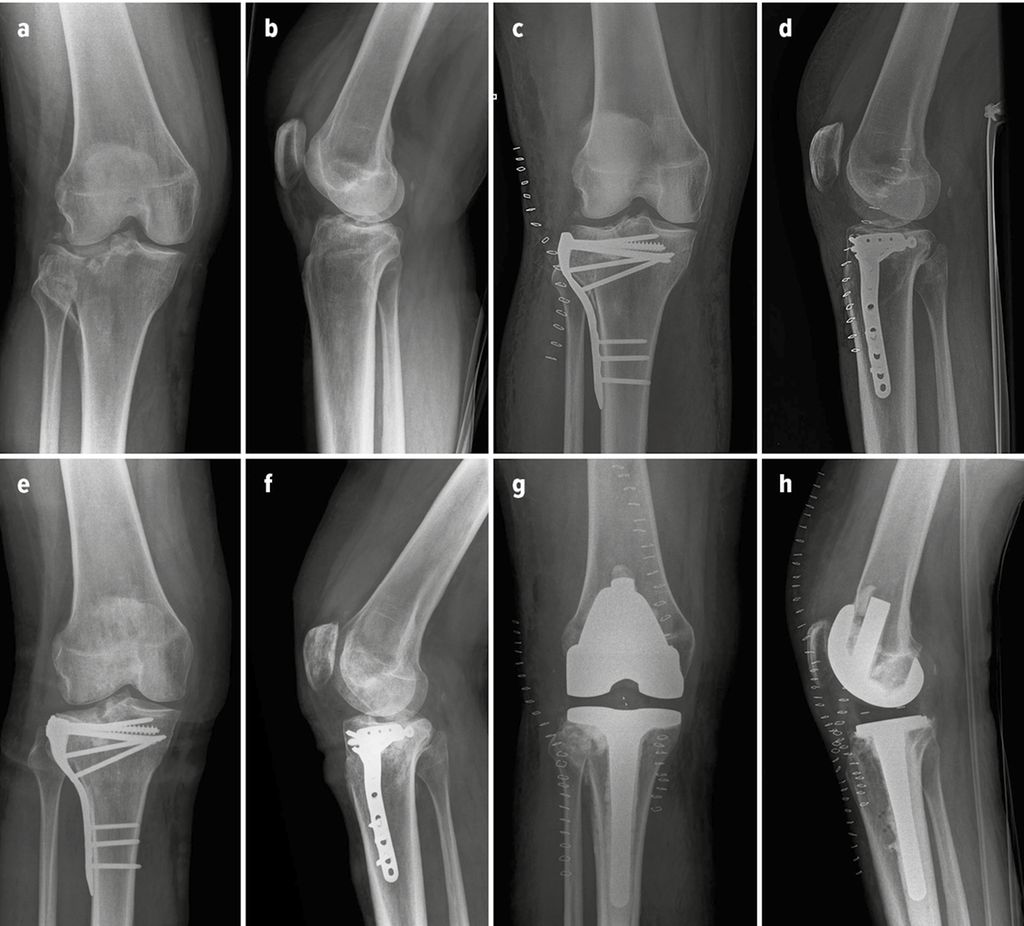

Source: tmartinctdc.pages.dev Primäre versus sekundäre Frakturendoprothetik am Kniegelenk Orthopädie & Traumatologie , Antwort von am 17.11.2012 ! Also ich hatte vor 16 Monaten eine Mikrofrakturierung Leider habe ich bei meinem operierten Knie nach 3,5 Monaten starke Schmerzen wenn ich einem bestimmten Winkel auftrete.Das Knie wird auch immer wieder dick , ist aber nicht entzündet